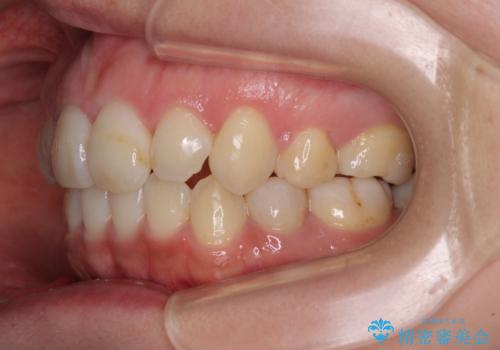

インビザラインによる矯正治療は、どれだけマウスピースを外す時間を短くできるかが成功の鍵となりますが、抜歯矯正ではよりシビアに要求されます。

こちらの患者様は、1日22時間以上を厳守してくださり、3年強で終えることができました。